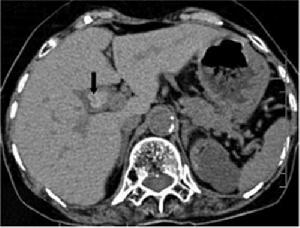

膽囊息肉CT圖示PLG為一組表現形式相同但卻包含很多不同病理狀態的膽道疾病。病理分類為非腫瘤病變與腫瘤性病變兩大類,後者又分為良、惡性。

3.內鏡超聲(endoscopicultrasonography,EUS)即經內鏡超聲掃描,是將超聲微小探頭安置在內鏡頂端,探頭為高頻,將內鏡插入消化道,進入十二指腸壺腹後此探頭更接近膽囊,可排除腸氣干擾或膽汁黏稠度等影響。EUS可將膽囊壁分為3層,內層為高回聲的黏膜及黏膜下層,中層為低回聲的肌纖維層,外層為高回聲的漿膜下層及漿膜層。如為息肉樣病變可見清晰的3層囊壁,而膽囊癌則囊壁的3層結構有不同程度的浸潤破壞。早期膽囊癌絕大多數是在結石和息肉等病變的掩蓋下發展的,早期缺乏特徵性聲像圖表現,鑑別困難。而EUS檢查觀察息肉樣病變與膽囊壁之關係,有助於鑑別診斷。朱燕陵等回顧分析了103例非結石性膽囊病變EUS檢查結果並與體表超聲及手術後病理進行比較,EUS檢查診斷正確率為75%,體表超聲為41.4%,EUS對膽囊息肉、膽囊癌、膽囊腺肌瘤診斷符合率為100%,體表超聲為55.6%。Sugiyama認為內鏡超聲(EUS)比BUS更準確,提供的圖像也更清晰。因194例PLG中,EUS判斷的136例非腫瘤性病變平均隨訪2.6年均未發現腫瘤;而BUS判斷的非腫瘤性病變中則有13%為腫瘤。EUS內層的回聲方式為細小聲點(tinyechonicspot)、聲點聚集(aggregationofechogenicspot)、微小囊腫(microcyst)及彗星尾征(comettailartifact)。如EUS證實既無細小聲點與聲點聚集,又無微小囊腫與彗星尾征時,應懷疑為腺瘤或癌腫。兩者無法鑑別,除非已浸潤至肝臟,但若為無蒂病變,則強烈提示為癌腫。結合組織學研究,一個細小聲點表示一群含有膽固醇泡沫的組織細胞,而無回聲區則為腺上皮增生。多個小囊腫和彗星尾征則分別為羅-阿竇增多和膽囊壁內結石所致。Gouma對31例PLG作CT與增強CT對比,CT僅發現14例(45%),而增強CT則為100%。因此,認為凡不增強CT已能發現的病變及增強CT發現的無蒂PLG均應診斷為腫瘤性息肉。有蒂與無蒂的診斷意義很大,20例有蒂PLG中6例為腫瘤(30%),而11例無蒂PLG中10例為腫瘤(91%)。增強CT診斷腫瘤性PLG的敏感性為88%,特異性87%,陽性預測率88%,陰性預測率87%,總準確率87%,結論為增強CT能鑑別腫瘤與非腫瘤性PLG,能可靠地篩選出應予切除的腫瘤性病變。